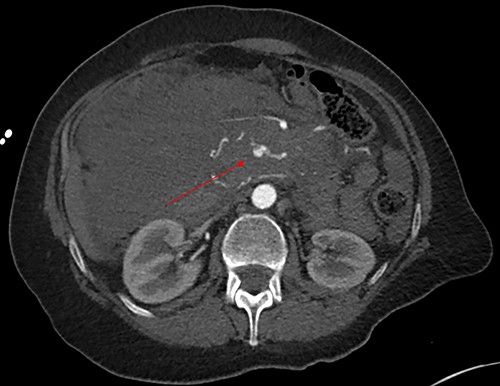

Initially, the main diagnosis considered was an aortic dissection. Other initial general surgical differentials were a perforated viscous or severe pancreatitis. Computed tomography (CT) angiogram showed a 6 mm pseudoaneurysm arising from a branch vessel 3 cm distal to the origin of the SMA. There was no active arterial blush; however, there was a large associated mesenteric haematoma (measuring 4.5 × 8.0 × 13 cm) with large volume haemoperitoneum (Figs 1–3). There was also a splenic artery aneurysm measuring 5 mm with no evidence of active haemorrhage. After the CT scan, she was noted to be haemodynamically unstable when lying supine, due to inferior vena cava compression by the mesenteric haematoma. A pillow was placed under her left lateral side to act as a wedge to reduce this. She proceeded to urgent angioembolization by interventional radiology, which confirmed the pseudoaneurysm on angiography (Fig. 4, left). The SMA was accessed and the aneurysm was successfully embolized with 3 mm diameter 15 cm length Ruby micro-soft detachable coil (Fig. 4, right).

Axial image with arterial phase, demonstrating the pseudoaneurysm arising from a branch of the SMA. There is no active arterial blush.